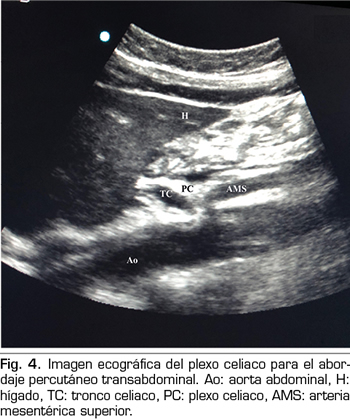

Figura 5